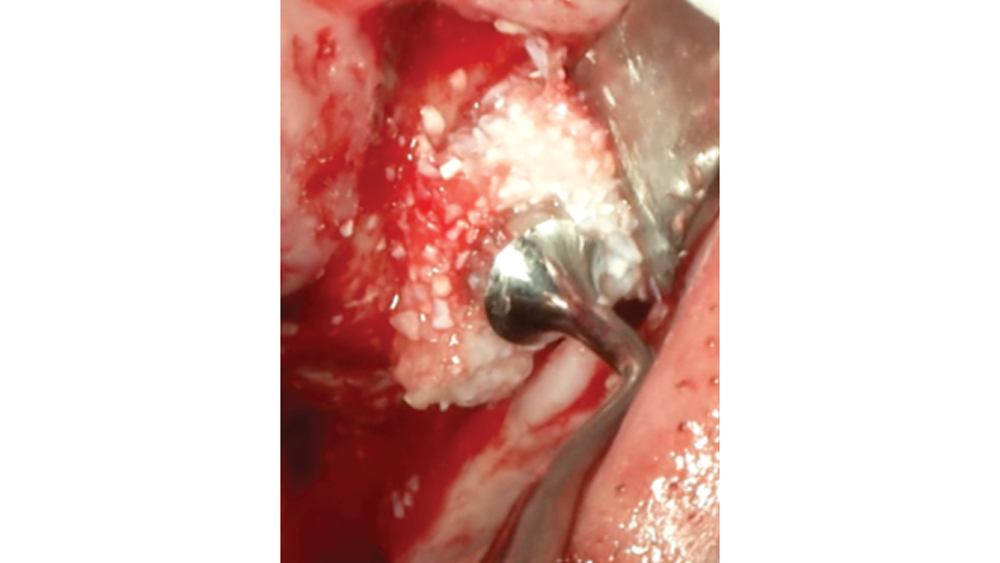

Bone graft putty is shown inserted into an osteotomy via osteotome sinus graft technique

Newport Biologics Bone Graft Putty Mineral-Collagen Composite is a calcium phosphate-based grafting material that becomes moldable upon hydration. It features a carbonate apatite structure similar to natural bone, combined with a type I collagen derived from bovine Achilles tendon. The mineral particles are dispersed within collagen fibers, forming a 3D matrix that is fully resorbed during the natural process of bone formation and remodeling. This bone graft putty is ideal for sites that require no movement of the graft material, such as areas of high muscle pulls or sinus augmentation procedures. Shown is bone putty inserted into an osteotomy via the osteotome sinus graft technique.